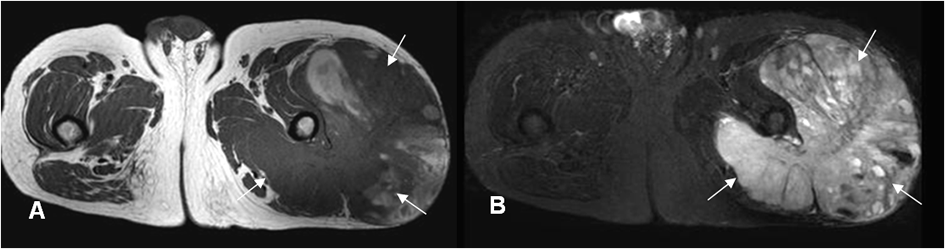

A: RM axial en T1 y B: RM axial en STIR. Tumoración de tejidos blandos en el muslo, que cruza compartimientos e invade los grupos musculares, correspondiendo a sarcoma de tejidos blandos.